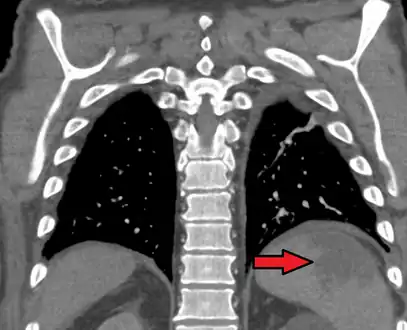

a, b) Splenic infarction. -

Splenic infarct seen on CT

An abdominal CT scan is the most commonly used modality to confirm the diagnosis,[3] although abdominal ultrasound can also contribute.[16][17][18]